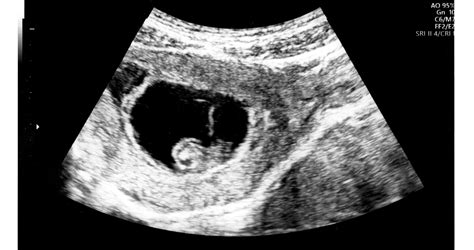

Az üres petezsák akkor alakul ki, ha a megtermékenyített petezsák megtapad a méhfalon, de az embrió kb. a hatodik hét után nem fejlődik tovább. A petezsák az, ami körülveszi az embriót és a magzatvizet, és a magzat táplálását, fejlődését segíti. Ez általában az ötödik hét körül már látható, ezt követően pedig nagyjából egy mm az átlagos növekedése naponta. A petezsák lehet kóros alakú vagy üres még az után is, hogy a szikhólyagnak láthatónak kellene lennie.

Mi történik az üres petezsák esetén?

Az esetek többségében az üres petezsák magától távozik a méhből, ami az első tünet lehet a feltételezett terhesség megszűnése. Sok esetben, ha progeszteron pótlás történik, az megakadályozhatja a vetélést, amíg a hormon szedése tart. Azonban a szervezet "nem fogadja el" a nem fejlődő terhességet, így a hormonpótlás abbahagyása után általában elindul a folyamat.